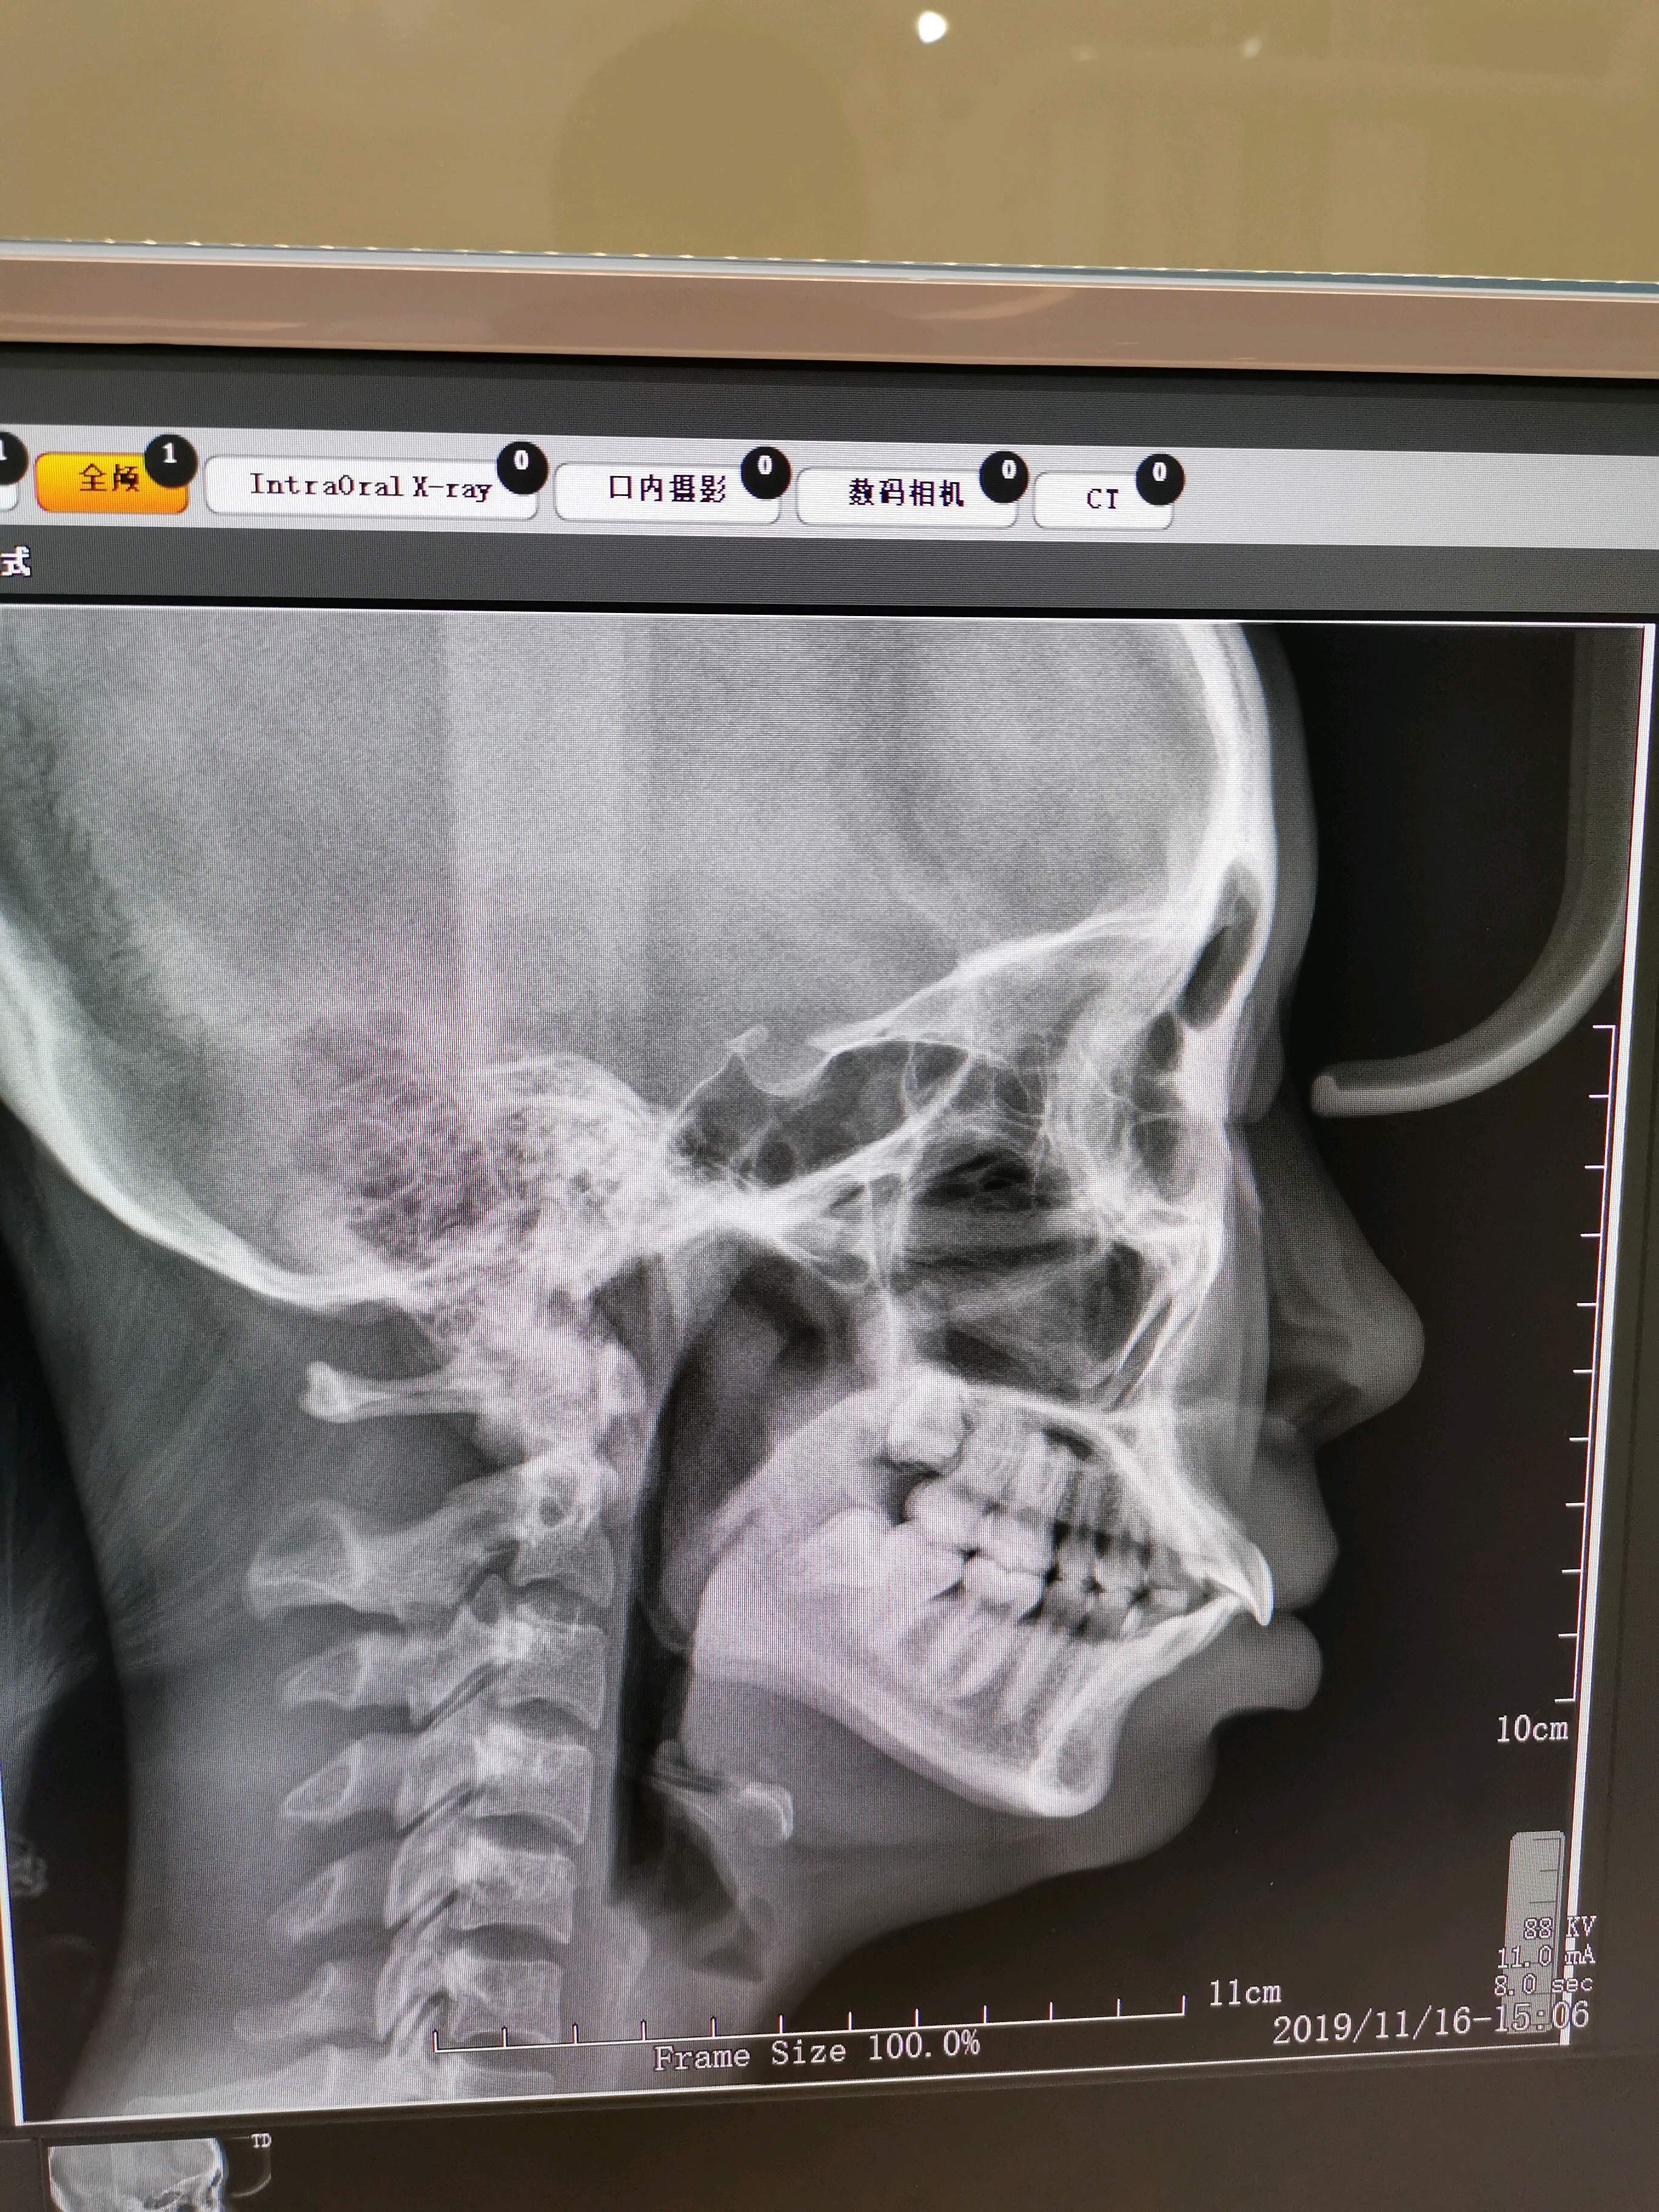

你好我这是骨性凸嘴还是齿性凸嘴以为不严重没想到凸嘴一点气质都没有

上颌前突矫正 下巴截骨前移!

常见的就是牙颌畸形,由于上颌骨发育过度,造成的牙槽骨向前突出;一般

也就是牙性前突的患者上颌骨是不突的,因此"牙性"前突中上前牙往前

上颌骨影响——比如黄绮珊,她的上颌骨就是过度发育,从侧面看

过于突出的上颌骨

嘴突有辣么多种看看你是哪一型之骨性前突

上颌骨突出